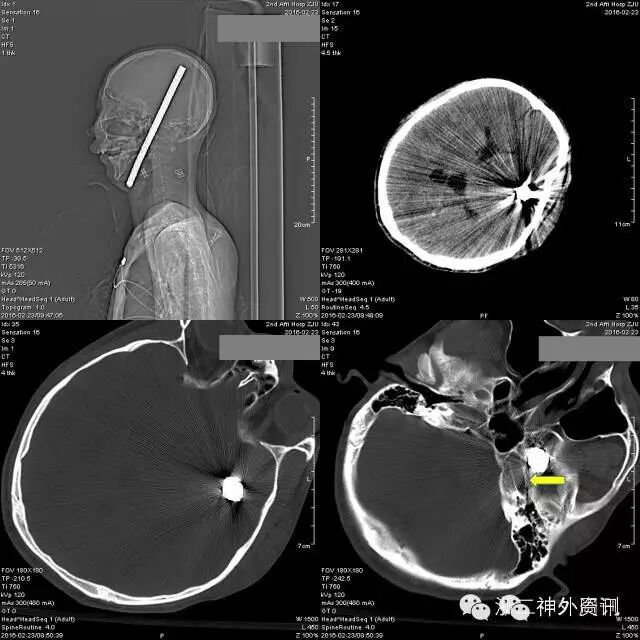

头颅CT提示:可见金属棒状物自右颈部颌下斜行经口咽、左侧鼻咽及中颅底,至左侧额颞部颅骨穿出,伴右侧颌下及上颈部皮下气肿,周边放射状伪影明显,周围结构显示欠清,左颞叶脑实质穿透,异物周边脑实质水肿,右侧脑室受压变形,局部中线结构轻度右偏。左顶部头皮软组织肿胀。左侧中颅底及左顶骨骨折,鼻骨骨折(见图2)。

图2. 头颅CT提示螺纹钢与左颈内动脉管贴近,最近处约2mm(箭头所示)。

颈动脉CTA示:两侧颈动脉周边未见明确血肿,金属异物与左颈内动脉管贴近(见图 3)。

图 3. 三维重建显示螺纹钢位置。